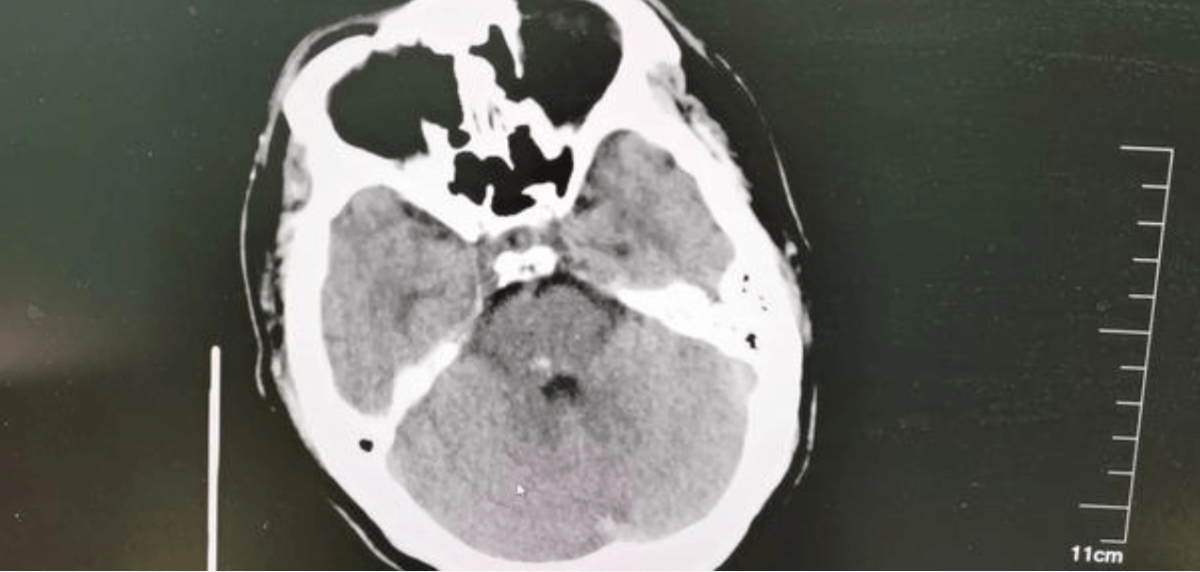

相关检查结果也出来了!血压:142/102mmHg , 头颅CT提示:右侧放射冠脑梗塞!医生告诉黄大哥夫妇 , 病情重 , 诊断急性脑梗死 , 需立即安排神经内科住院!